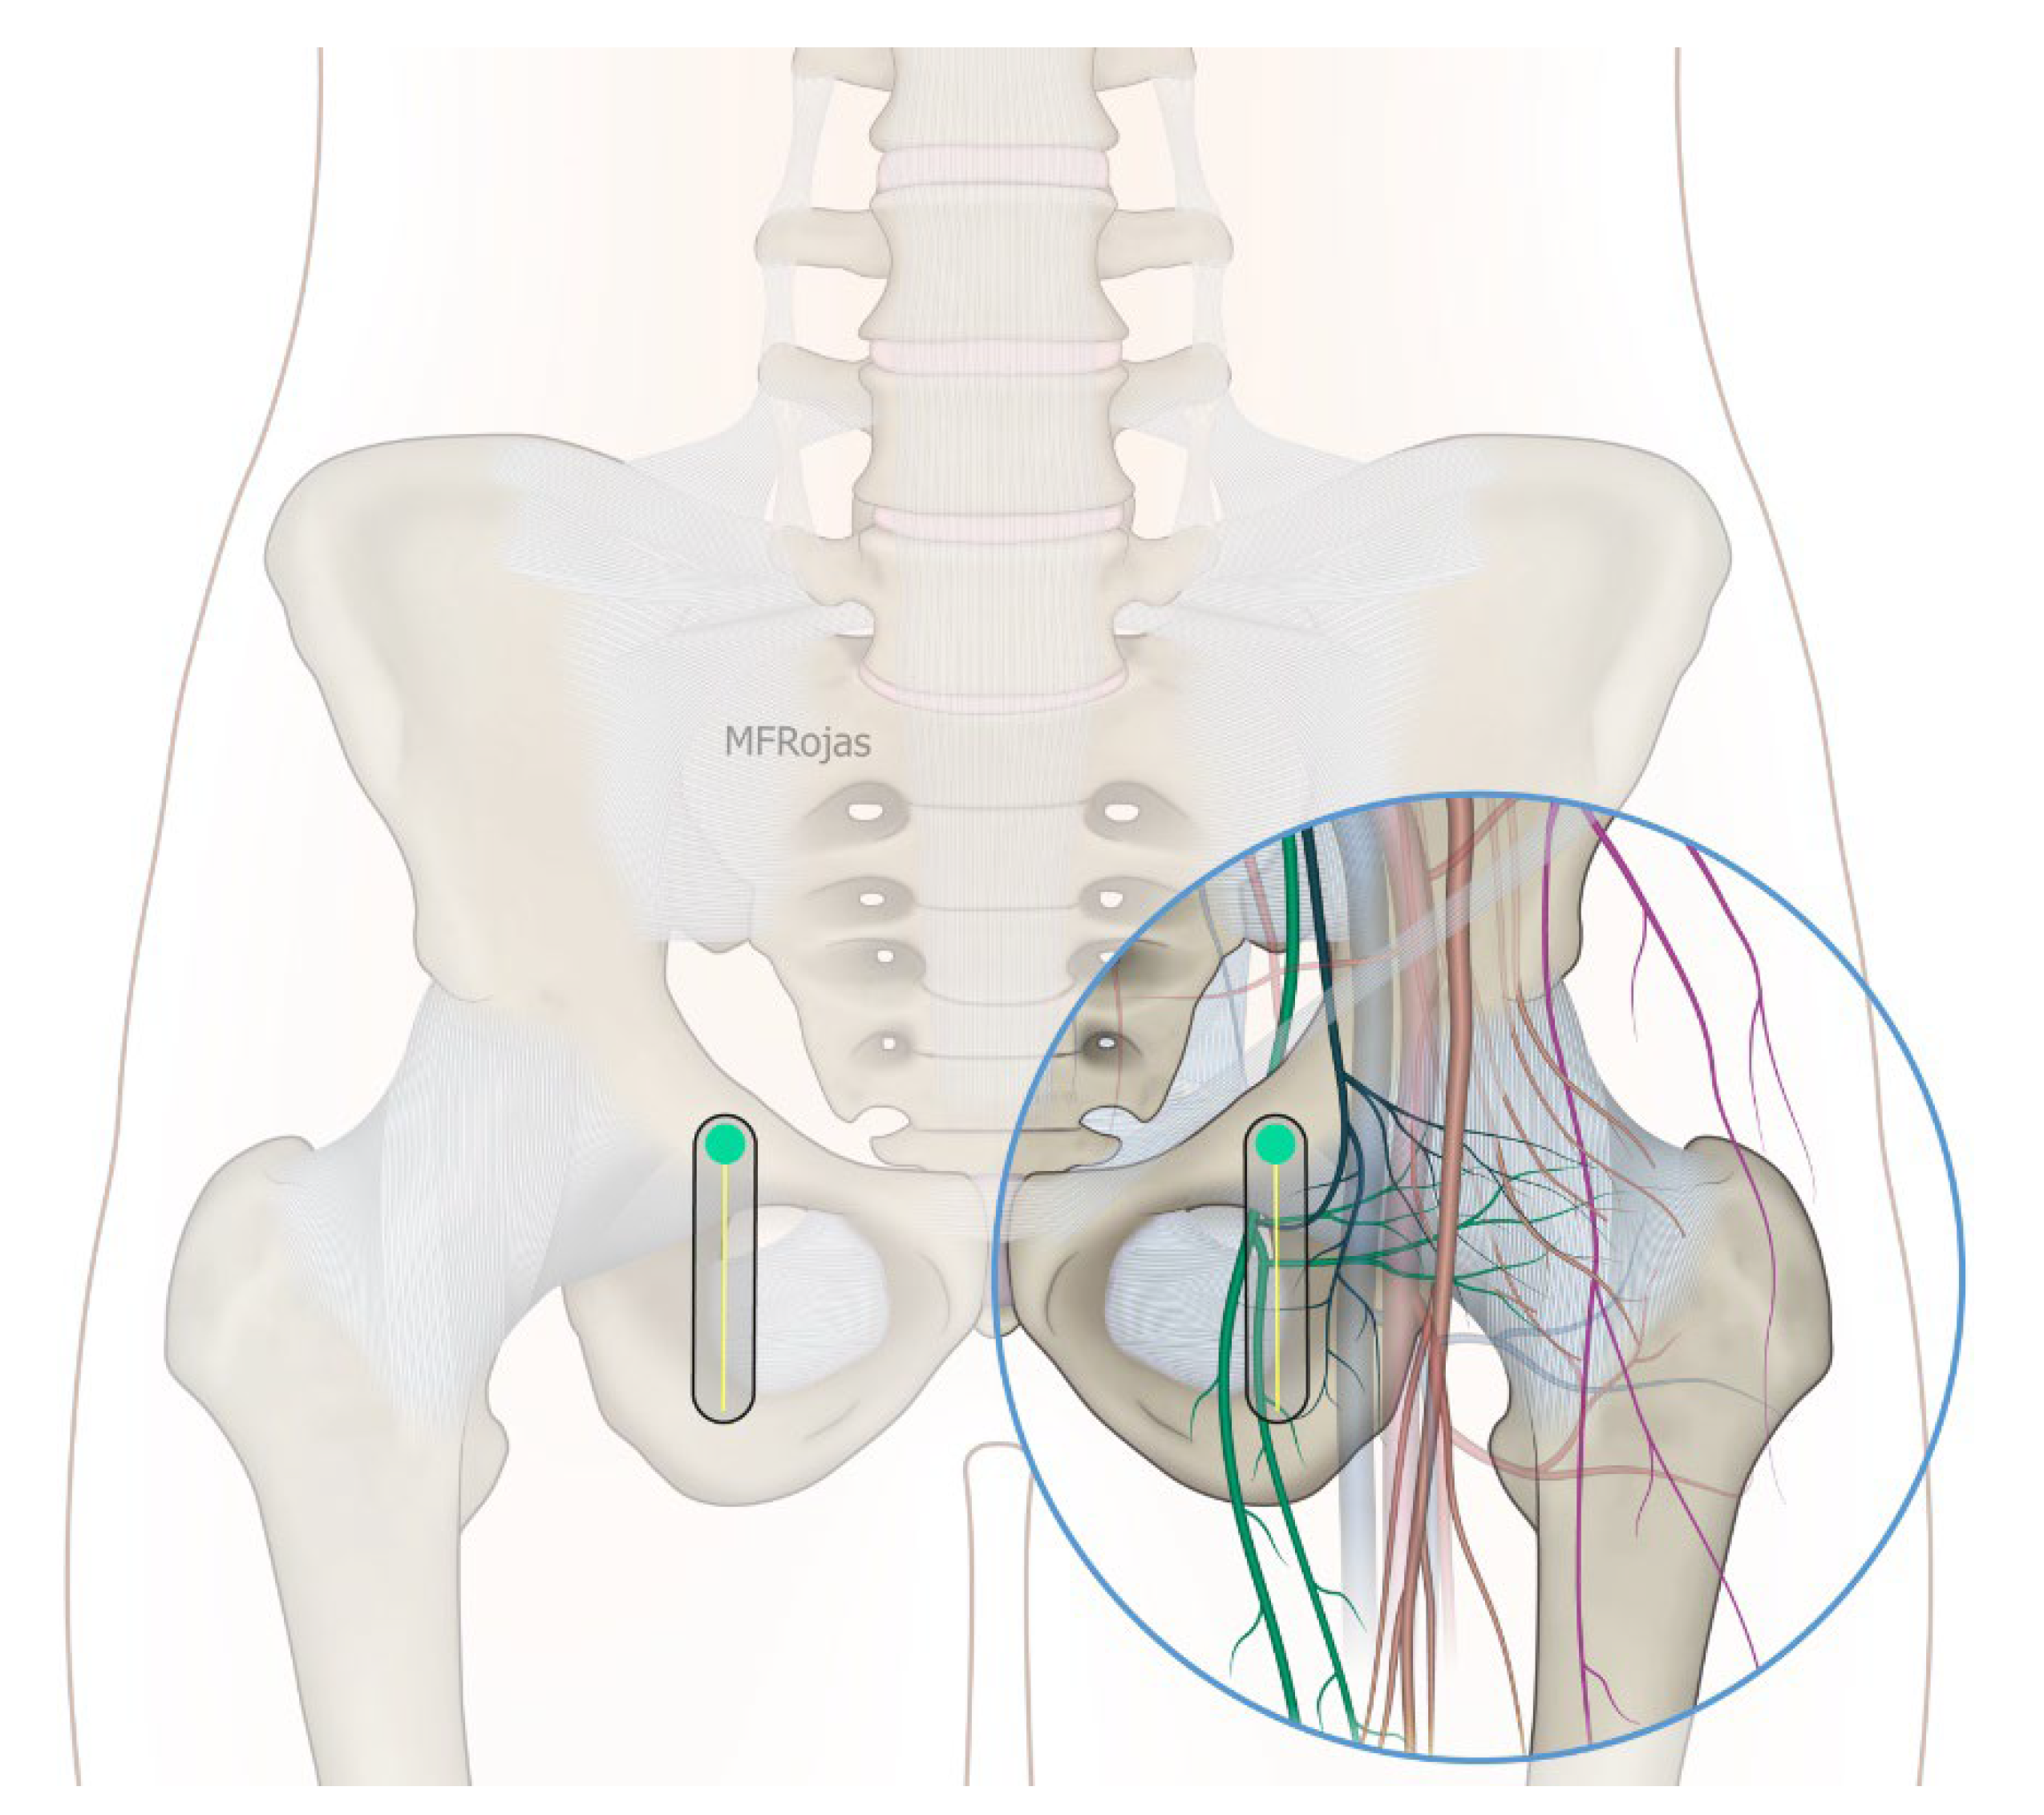

The growing impact of fragility hip fracture on the healthcare system and on society has become a major concern worldwide. Despite the advances in perioperative medicine and anaesthetic care, a minority of frail patients are still too ill to be surgical candidates. Hip fracture analgesia generally includes non-pharmacological modalities, oral and injectable analgesics, traction and regional nerve block [1,2]. However, given the complexity of medical comorbidities in this patient population, pain management of hip fracture is not a one-size-fits-all recipe [1]. Acupuncture, relaxation therapy, and transcutaneous electrical nerve stimulation (TENS) may be associated with potentially clinically meaningful benefits, but no firm conclusion can be drawn from the current evidence [1]. Comorbidities may also prohibit the use of these therapies, for instance, pacemakers and anticoagulants. Simple non-opioid analgesics are often insufficient to treat dynamic pain adequately, whereas opioid analgesics can cause disturbing side effects in this patient population, such as dizziness, nausea and vomiting, sedation and even respiratory depression. Traction does not reduce the intensity of acute pain, and patients also remain bed-ridden during this treatment [2]. Regional nerve blocks, such as Pericapsular Nerve Group (PENG) block, fascia iliaca block and femoral nerve block, can effectively manage fracture pain, especially if a catheter is inserted [1,2,3]. Nevertheless, the benefit from a single shot regional nerve block can usually last for 1 to 3 days whilst there is an infective concern if a block catheter is placed for weeks. Community management of the catheter is also a practical concern in our locality. Partial hip denervation hence becomes a treatment option to provide long-lasting analgesia by a single intervention. With the sophistication of ultrasound technology coupled with a greater understanding of hip joint innervations in recent cadaveric studies (Figure 1), there has since been a venture to develop an ultrasound-guided approach to denervate the hip joint. The first such approach was described by Sasaki et al. in 2018 [4], where alcohol was infiltrated superficially over the ligaments encasing the anterior hip joint, namely the iliofemoral and pubofemoral ligaments. Subsequent to our case series demonstrating the efficacy of the conventional approach, which consisted of a PENG injection and an oblique approach to the obturator nerve articular branches (ONAB) [5], we noticed there were circumstances in which the conventional approach did not work well, and enormous technical difficulties were encountered in terms of needle trajectory.

Figure 1. Nerves supplying the hip joint and their relationship to the femoral vessels. Reproduced with permission from Dr Maria Fernanda Rojas Gomez (Bucaramanga, Colombia).